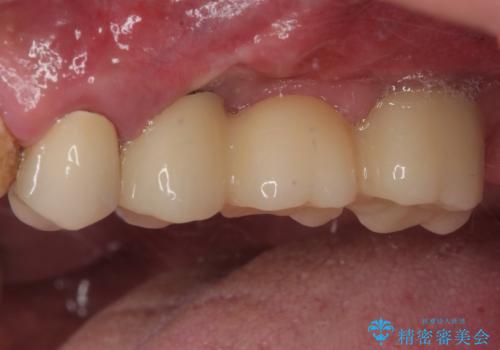

割れてしまった奥歯 抜歯即時埋入インプラントによる短期間治療

- 土台の歯が割れてしまって、歯がグラグラしているとのことで来院された患者様です。

いずれの歯も抜歯が必要な状態であり、抜歯即時埋入によるインプラント治療を行うこととしました。

右上奥歯は骨欠損の範囲が広いため、抜歯即時埋入は可能であっても、即日で仮歯を装着する即時荷重は難しいと判断されたため、手前の歯まで仮歯を装着することとしました。

術後にインプラントの安定値を測定し、十分な値が達成された後、速やかにセラミッククラウンにて補綴治療を行うこととしました。